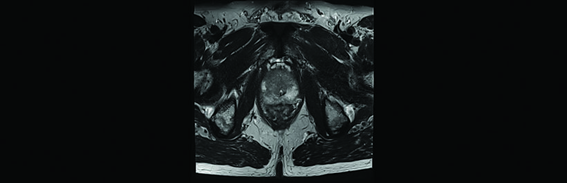

No caso do paciente abaixo, o histórico médico apresentou uma biópsia prévia negativa. Porém, devido ao elevado nível de PSA encontrado, foi feita uma ressonância magnética multiparamétrica, ou mpMRI (Fig. 1). O exame mostra uma lesão circunscrita suspeita no lado apical direito da próstata.

Imagem de RM mostrando uma área de lesão circunscrita suspeita do lado direito da próstata.